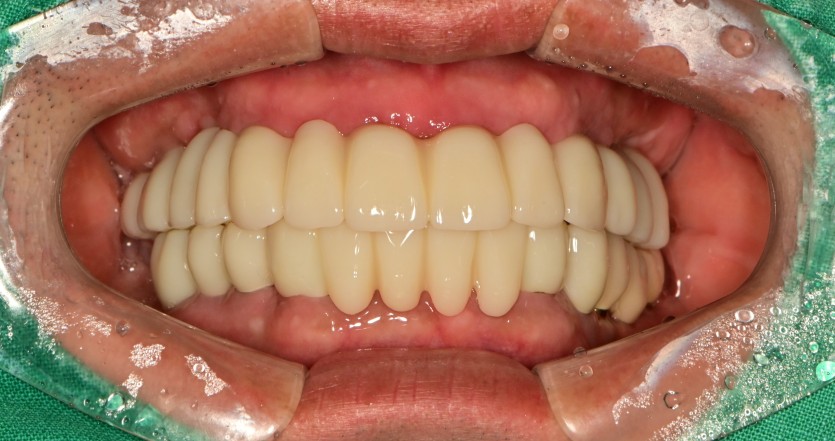

전체 임플란트 증례입니다.

16개의 임플란트로 완성하였습니다.